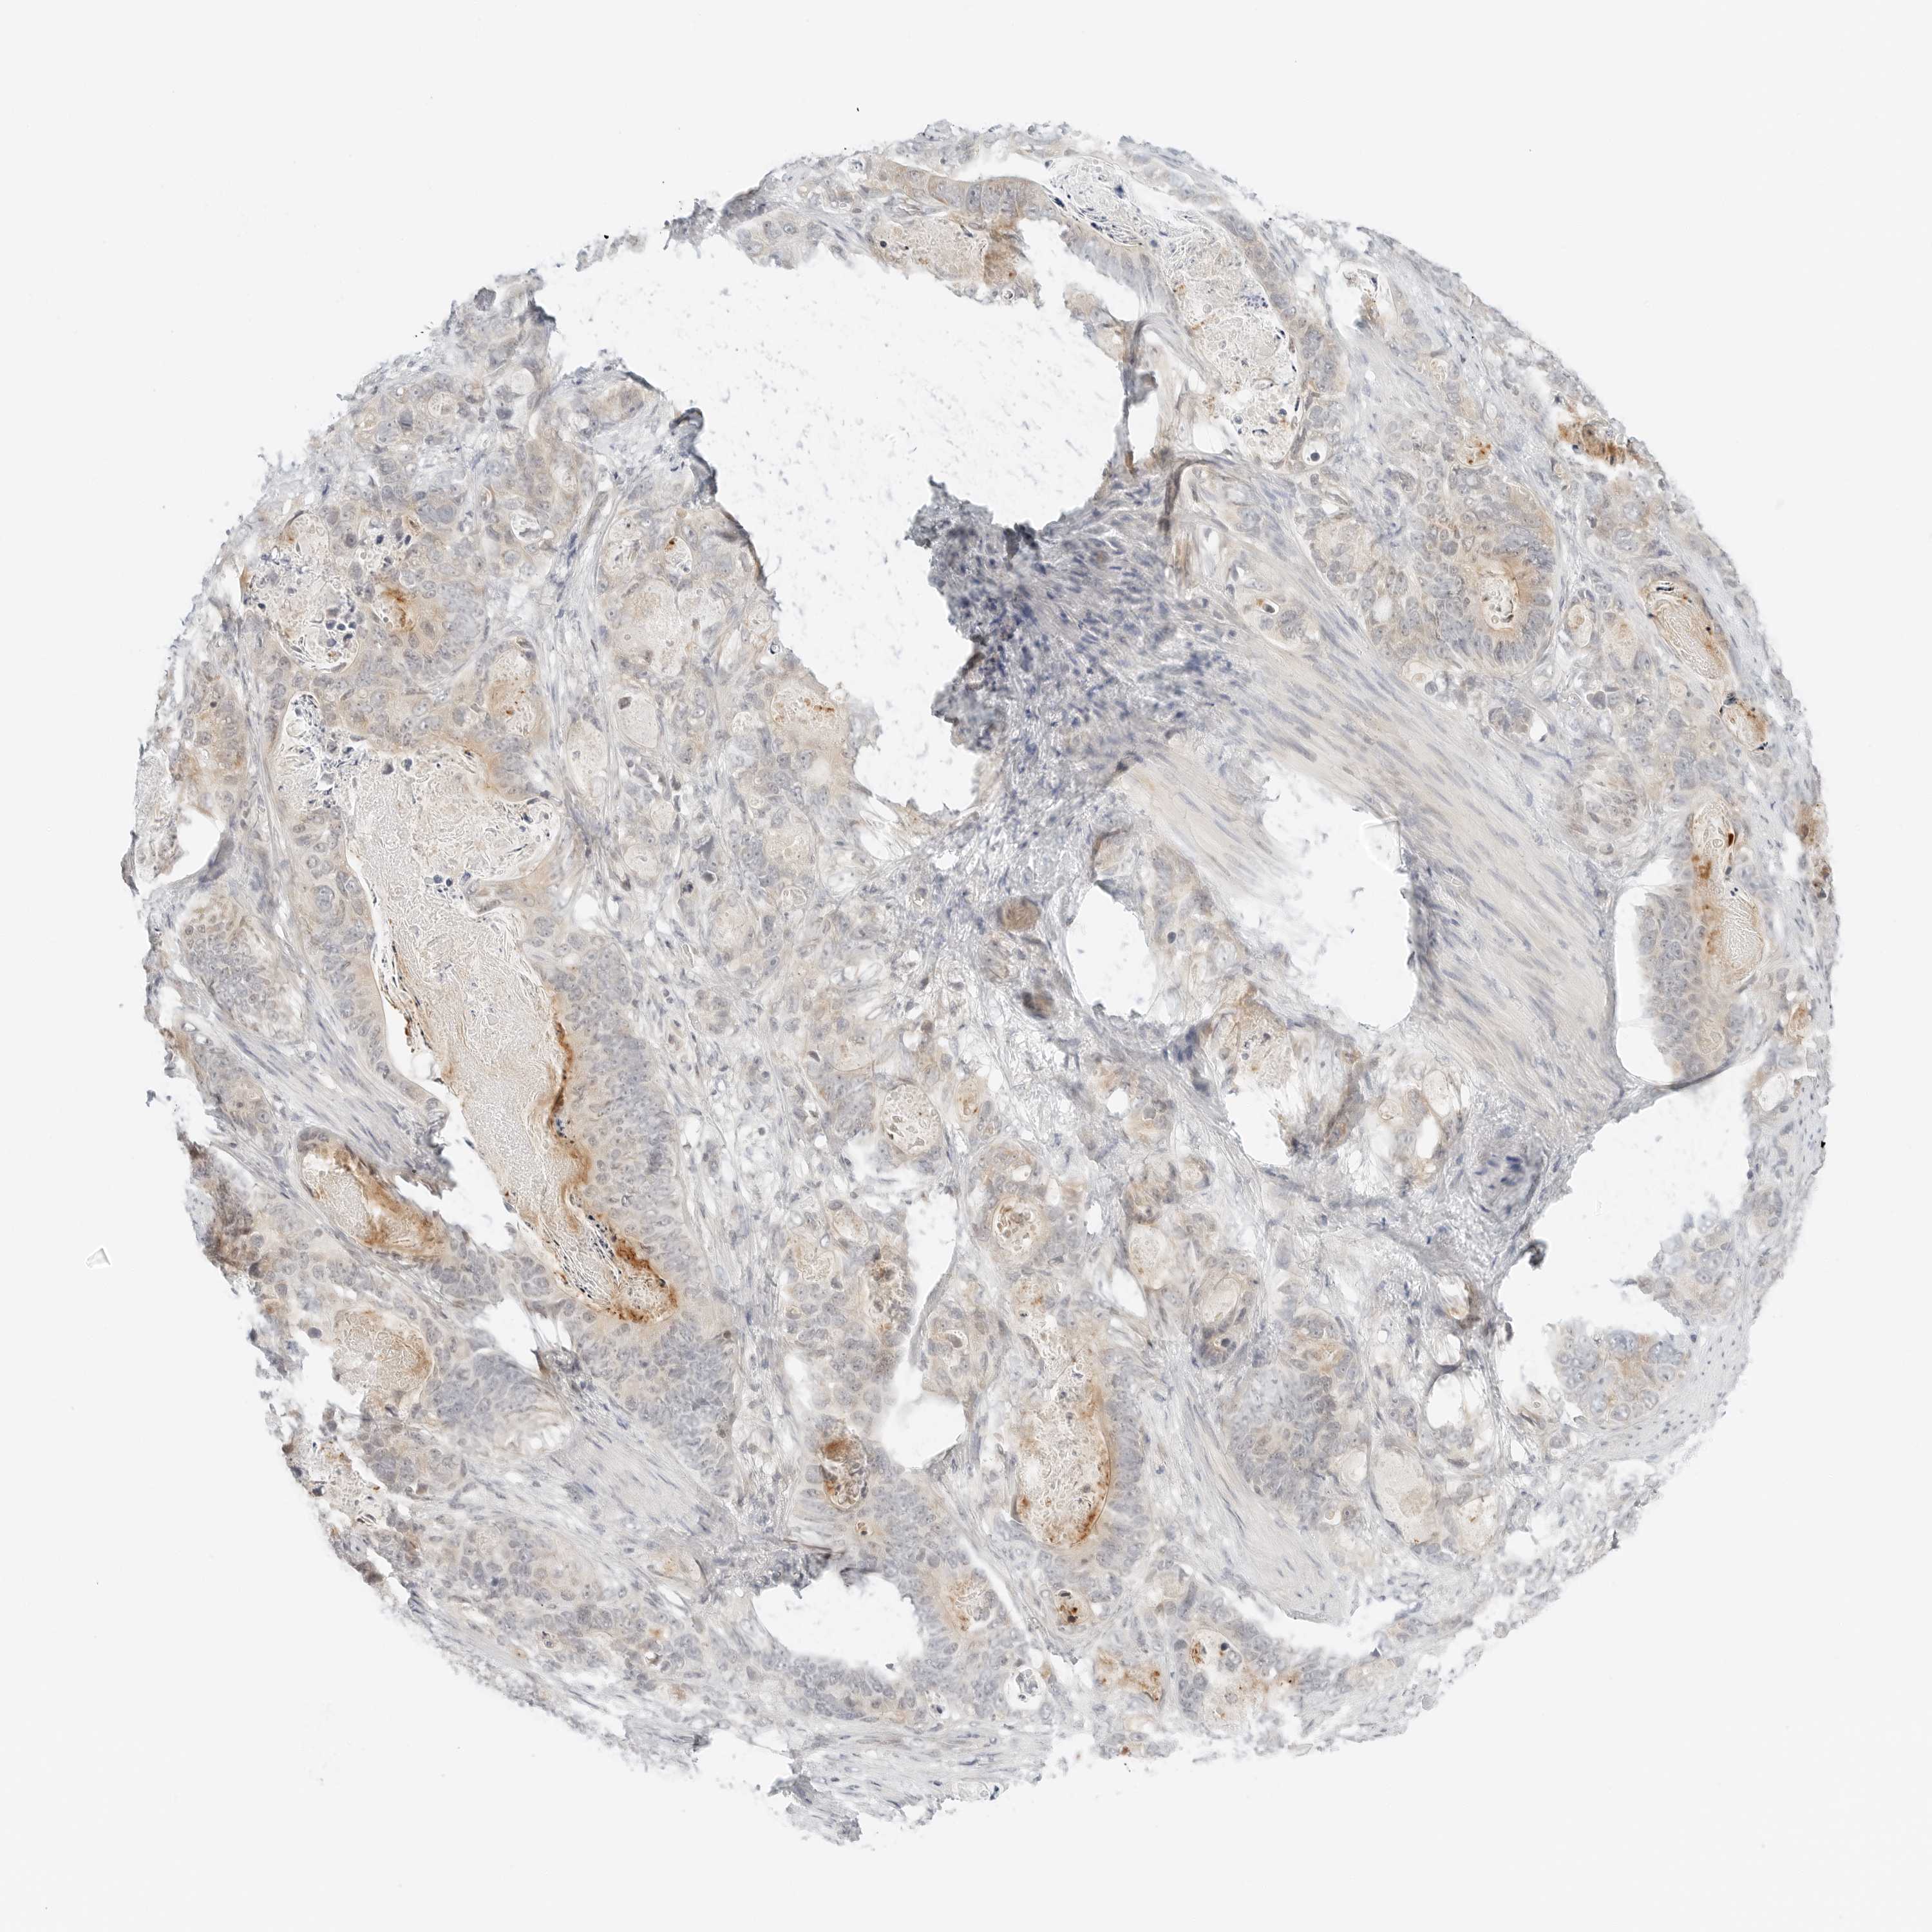

STOMACH CANCER - Protein expressioni

A mouse-over function shows sample information and annotation data. Click on an image to view it in a full screen mode. Samples can be filtered based on level of antibody staining by selecting one or several of the following categories: high, medium, low and not detected. The assay and annotation is described here.

Antibody stainingi

Antibody staining in the annotated cell types in the current human tissue is reported as not detected, low, medium, or high, based on conventional immunohistochemistry profiling in selected tissues. This score is based on the combination of the staining intensity and fraction of stained cells.

Each image is clickable and will lead to virtual microscopy that enables deeper exploration of all samples and also displays staining intensity scores, fraction scores and subcellular localization as well as patient and tissue information for each sample.

Antibody HPA028602

Antibody HPA028686

Adenocarcinoma, NOS